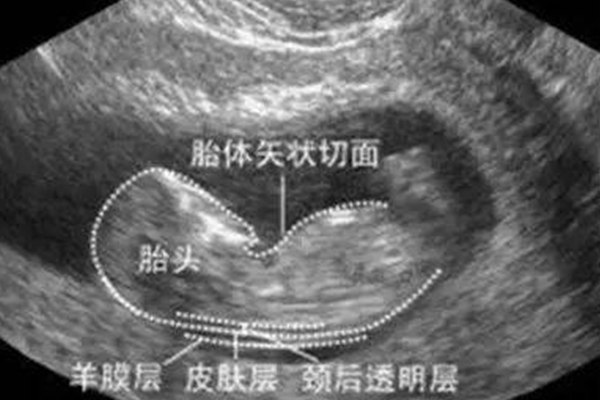

nt檢查寶寶最佳姿勢圖解

孕婦在做nt檢查的時候,對寶寶的姿勢有較高的要求,通常需要胎兒面部朝上,面向孕婦腹部,這個是做nt檢查的最佳姿勢,此時可以清楚檢查胎兒頸項透明帶厚度。一般來說,做NT檢查時,最佳時間是懷孕11-13周+6,如果小於或者大於這個月份,則NT測量都不準確。胎兒姿勢一定要仰臥,面向母親肚子,才能清楚的查出頸項透明帶厚度。

寶寶面部朝上才是最佳nt檢查姿勢

在現實生活中,孕婦接受NT檢查,應要求胎兒保持正面朝向母體腹部面板,且處於中立位,頭部與脊柱成一直線,如果孕婦做NT檢查(頸後透明帶掃描),胎兒不是面朝上,而是出現其他體位,容易胎兒頸部過度伸展或部分彎曲,從而影響檢測結果的準確率,導致測試結果不準確。

通常情況下,nt檢查最佳時間在懷孕11-13周左右,通過檢測胎兒頸部皮下最厚透明層的厚度,評估胎兒患21-三體綜合徵的風險,正常數值為小於3mm。如果胎兒頸部過度伸展可能會使測量值比實際數值要高,當頸部彎曲時,測量值可能會比實際數值要低。